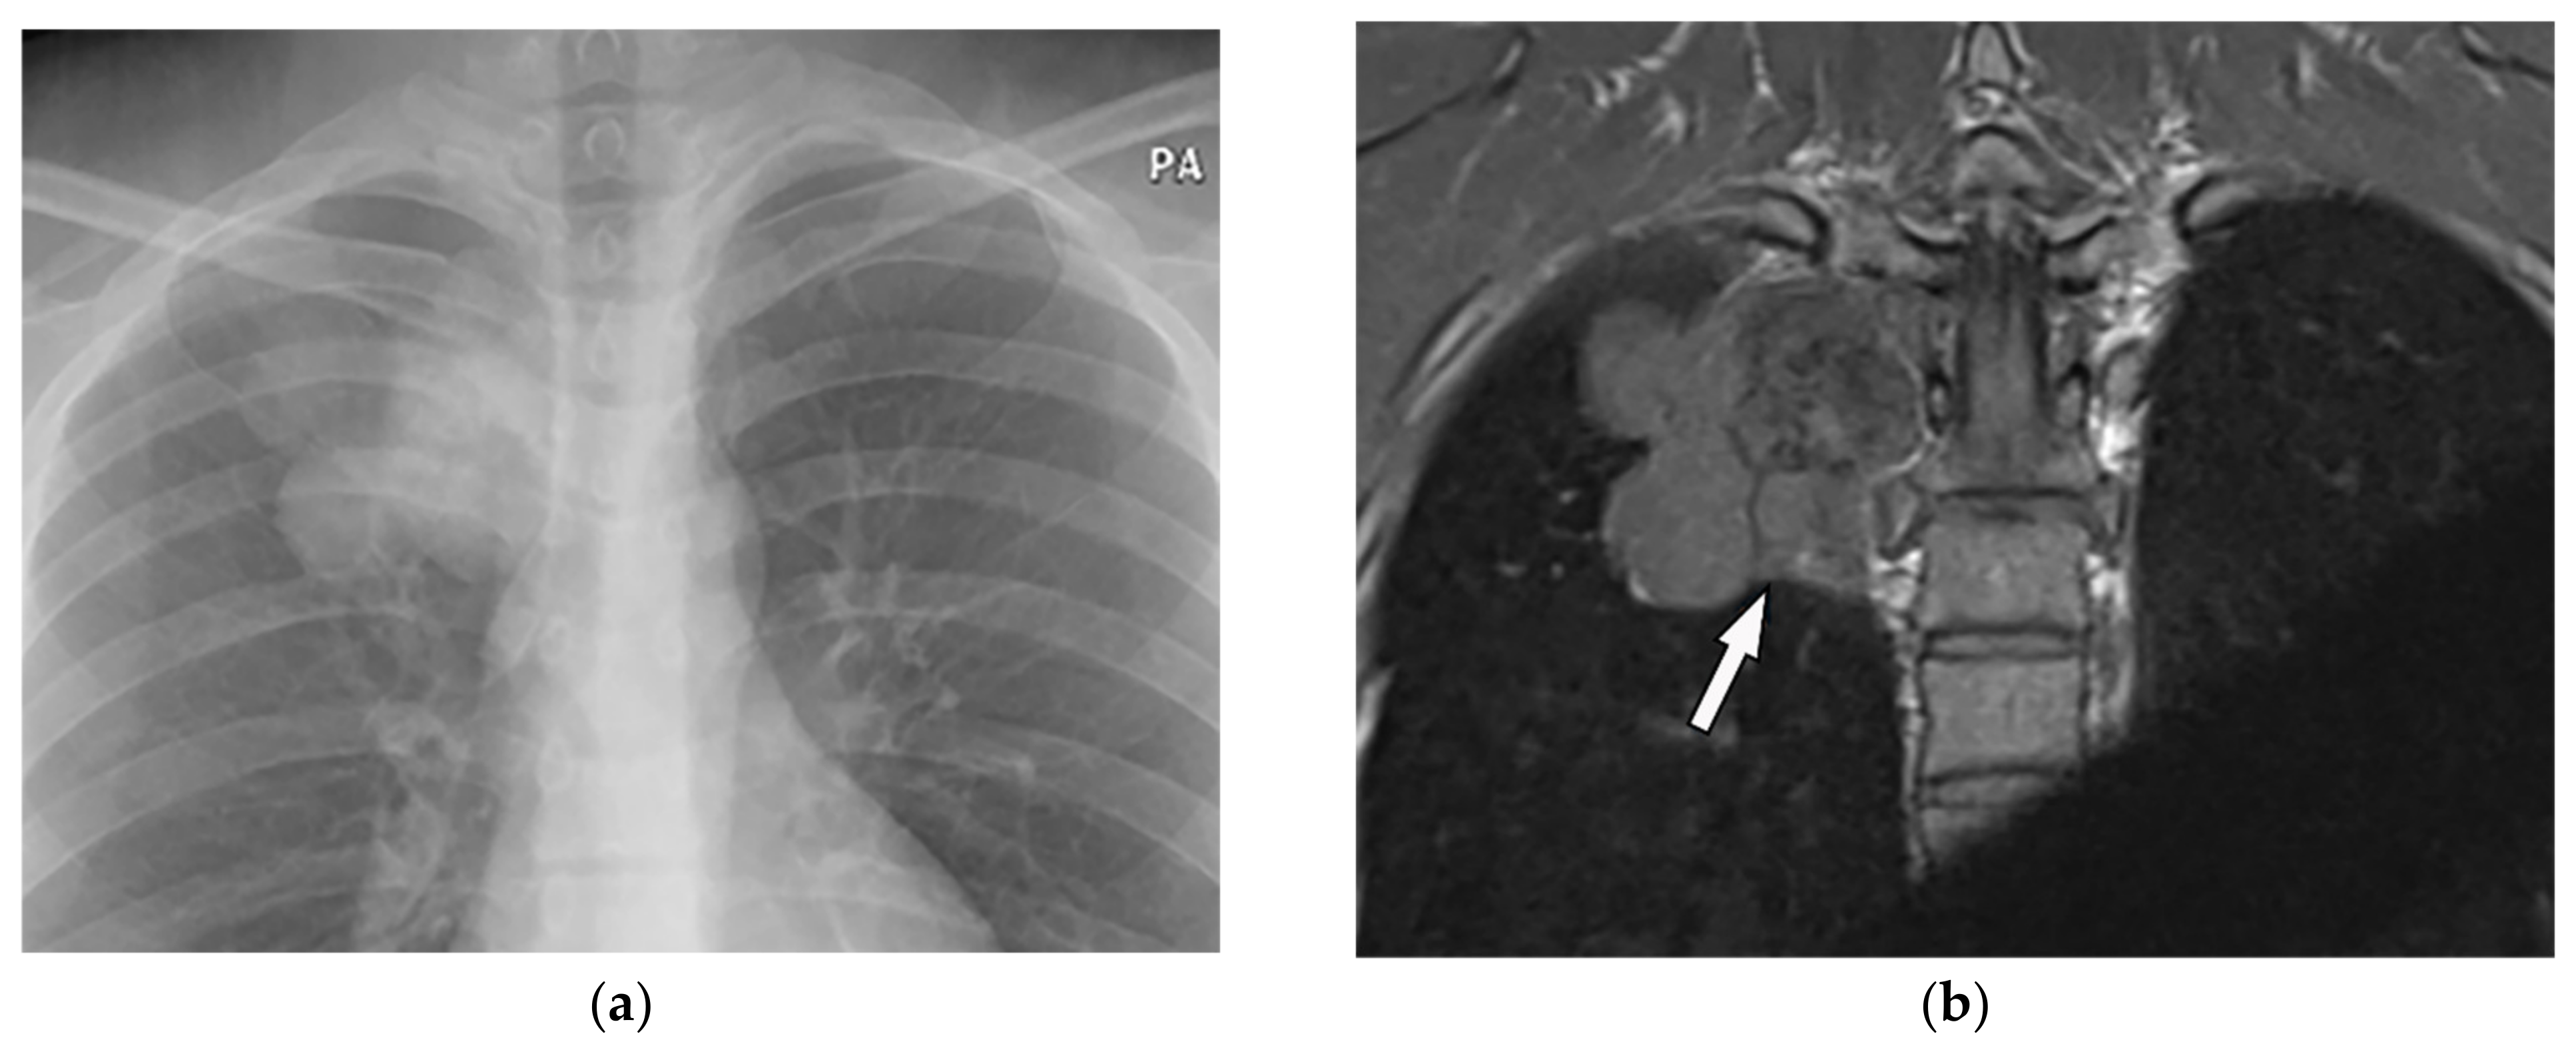

| Solitary Plasmacytoma of the Bone | Extrapleural mass with well-circumscribed margin and “soap bubble” appearance and rare calcification, multicystic expansion | T1W: hypointense T2W: hyperintense |